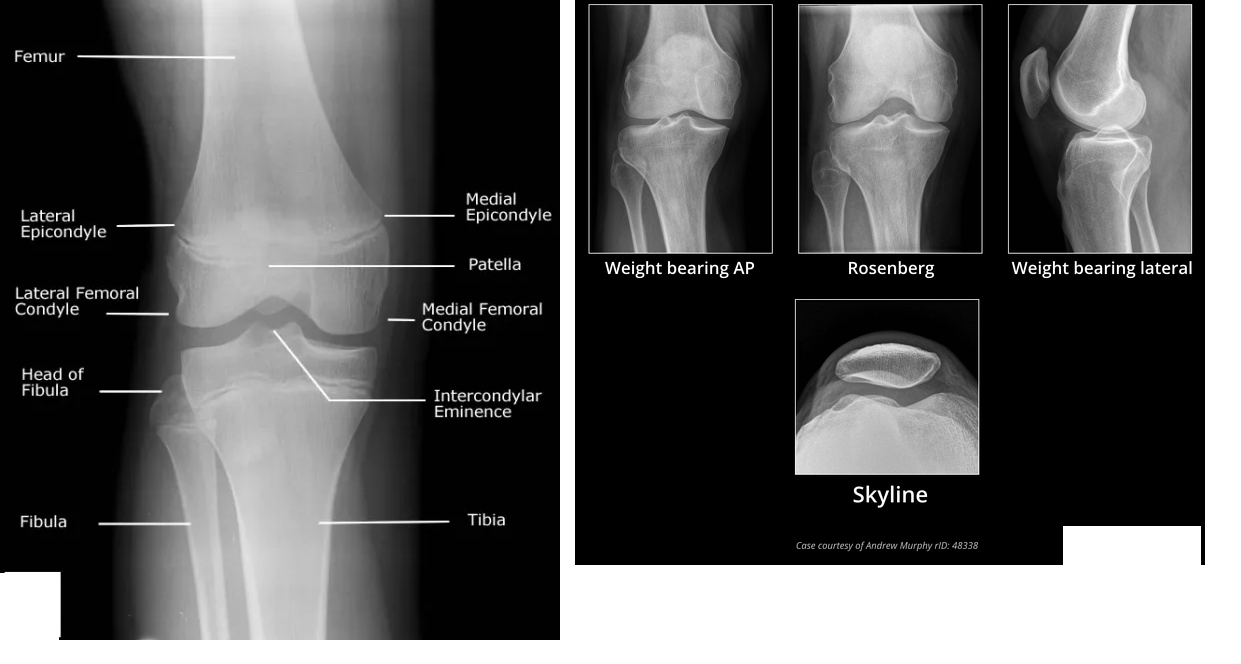

Figure 1: Diagrammatic representation of the tibial plateau anatomy.

The tibial plateau is the expanded, flat superior surface of the tibia, divided into medial and lateral condyles by the intercondylar eminence (tibial spines).

* Medial Tibial Condyle: Typically larger, stronger, and more concave than the lateral condyle. It bears approximately 60% of the axial load. The posteromedial aspect is particularly robust.

* Lateral Tibial Condyle: Smaller, weaker, and convex, making it more susceptible to depression fractures. Its anterior and posterior slopes are significant for knee kinematics.

* Intercondylar Eminence: Consists of medial and lateral tibial spines, which provide attachments for the anterior and posterior cruciate ligaments. Fractures involving the eminence can lead to knee instability.

* Tibial Tuberosity: Located anteriorly, serves as the insertion site for the patellar tendon. Its integrity is important for extensor mechanism function.

* Metaphyseal Flare: The region immediately distal to the articular surface, composed of highly vascular cancellous bone. It provides crucial support for the articular fragments and is often comminuted in high-energy injuries.